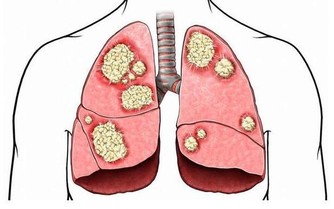

主食中的澱粉和醣類在滿足機體的需求之後,富裕出來的就會變成脂肪存積起來,如果脂肪過多,就會變成大眾理解的樣子,跑進肝臟裡面,引起脂肪肝。